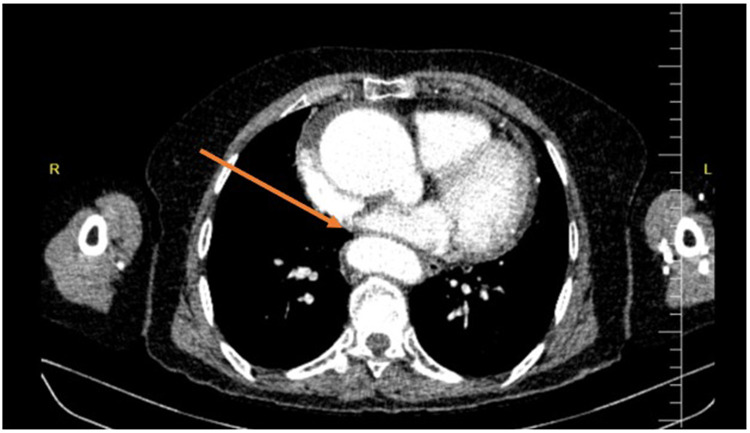

Case presentation: The patient presented with chest discomfort, dyspnea, and dysphagia for liquids and solids. Imaging revealed esophageal compression due to ascending aorta dilation. The dysphagia persisted despite pharmacological management, leading to the decision that surgical intervention was too risky. We placed a percutaneous endoscopic gastrostomy (PEG) tube to maintain nutrition, stabilizing her condition and improving her quality of life.